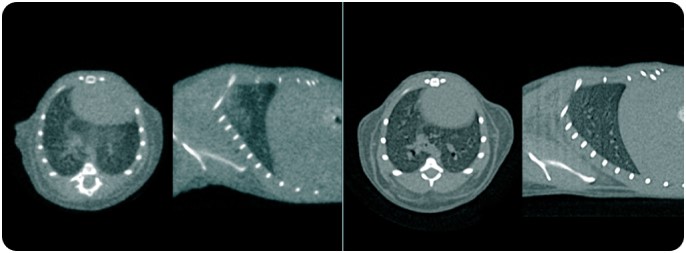

Range of CT only Applications: Rabbits

Range of CT only Applications:

Mice Pulmonary